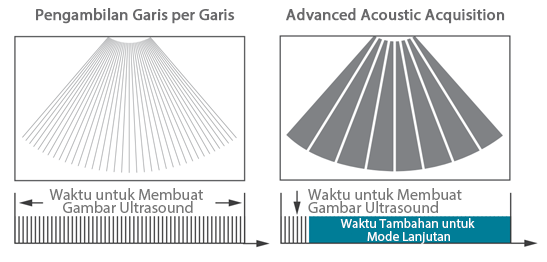

Sejak didirikan, Mindray terus mencari cara baru untuk meningkatkan keandalan diagnostik. Didukung Teknologi ZONE Sonography? terkini, platform ZST+ baru Resona 7 meningkatkan kualitas gambar ultrasound melalui pengambilan zona dan pemrosesan data saluran.